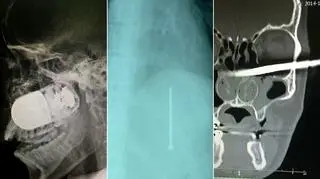

Granat w głowie, operacja na parkingu

Chirurdzy wyjęli granat z twarzy żołnierza

Lekarze z Kolumbii uratowali żołnierza, który trafił do nich z granatem wbitym w głowę. Medycy przeprowadzili operację na parkingu z powodu obawy, że ładunek eksploduje.